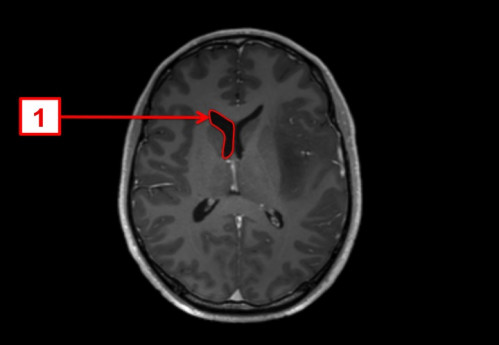

ICD: C71.9

ICD: R47.0

ICD: R51

23-jähriger Mann. Bereits seit Jahren plagen ihn Kopfschmerzen, die vor allem bei körperlicher Belastung auftreten. In den letzten Tagen fühlte er sich zunehmend unwohl, die Kopfschmerzen sind nun auch in Ruhe vorhanden.

Seit gestern Abend erbricht er sich mehrmals, und spricht, als ob er betrunken wäre.